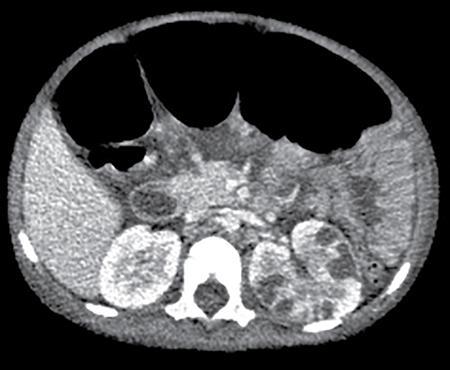

Anmol Bhatia, Ajay Prashanth Dsouza, Kushaljit Singh Sodhi Urinary tract infection (UTI) is a common cause of febrile illness in children, second only to respiratory tract infections. The incidence before 14 years of age ranges from 3%–10% in girls and 1%–3% in boys; however, the incidence is more in boys during infancy. The clinical spectrum in increasing order of severity ranges from asymptomatic bacteriuria and cystitis to acute pyelonephritis and septicemia. Urinary tract anomalies, prematurity, indwelling urinary catheters, lack of circumcision in boys and high-grade vesicoureteral reflux (VUR) are some of the common predisposing factors. Although the clinical outcome is good in most patients, a few may develop long-term complications like hypertension, chronic renal insufficiency and end-stage renal disease. Given the poor localizing signs and the dreaded complications, a high degree of clinical suspicion, prompt diagnosis and treatment and tailored follow-up play pivotal role in management of these patients. Urine culture is the most important tool to establish the diagnosis and identify the causal pathogen, Escherichia coli being the most commonly isolated bacteria. Midstream clean catch urine sample is used in toilet-trained children while the sample is often obtained by suprapubic aspiration or transurethral catheterization in younger age group. A colony count of >105 CFU/mL of a single species in a midstream clean catch sample is confirmatory. Although imaging can aid in the diagnosis of an ongoing UTI, the main role lies in identifying the associated urinary tract abnormalities and also to look for the extent of consequent renal insult. Some of the common anatomic abnormalities predisposing to recurrent and complicated infections include VUR, congenital pelviureteric junction (PUJ) obstruction, ureterocoele, posterior urethral valve, ureteral duplication and neurogenic bladder. The imaging modalities commonly used in children are ultrasound (US), which helps in detection of structural anomalies, hydroureteronephrosis, urinary tract stones and renal scars; voiding cystouretherography (VCUG) for detecting VUR and 99mTc-labelled dimercaptosuccinic acid (DMSA) scans to look for renal scars. US is often used as the first-line imaging modality because of its easy availability, low cost, non-invasiveness and lack of ionizing radiation. UTI, when confined to the lower genitourinary tract, frequently called as cystitis, reveals diffuse bladder wall thickening (Fig. 10.8.1A) with hazy margins on grey-scale US, which may show increased vascularity on Doppler (Fig. 10.8.1B). Floating echoes in the urine are commonly seen. The distal ureter may also be dilated and show mural thickening. Since UTI confined to bladder is mostly uncomplicated, it does not usually warrant a further imaging workup. However, in cases of severe bladder trabeculations, unilateral gaping ureteral ostium, open bladder neck, follow-up for bladder outlet obstruction, dysfunction or VUR may be indicated after the acute infection settles. Inflammatory response to the infection leads to swelling and decreased perfusion in renal parenchyma. Findings on intravenous urography (IVU) include renal enlargement, a diffuse or patchy striated nephrogram with delayed opacification and effacement of pelvicalyceal system. On renal US, diffuse or localized renal enlargement may be the only finding. Other typical findings include altered parenchymal echotexture, usually hypoechoic (Fig. 10.8.2) but may be hyperechoic, along with poor corticomedullary differentiation. Colour or power Doppler study reveals reduced vascularity. On 99mTc DMSA or glucoheptonate scans, photopenic defects due to reduced accumulation of renal cortical tracers are seen. The defects may be solitary, multiple or may involve the entire kidney giving a mottled appearance. DMSA renal scintigraphy with a sensitivity of 99.9% is the imaging modailty of choice for diagnosing acute pyelonephritis (APN). Among the patients with UTI, 50%–91% show defects on nuclear scans, suggestive of acute pyelonephritis. When both VUR and APN are present, scintigraphy is abnormal in 79%–86% of children. Permanent scars are known to occur in 38%–57% of children diagnosed with APN on nuclear scan, not withstanding the grade of VUR. 99mTc DMSA scan is the imaging modality of choice for detection of renal scars and they also appear as photopenic defects; however, the temporal course of study helps to differentiate it from APN. Thus, follow-up scanning at 3–6 months may be suggested to detect if the kidney has healed or scarred. CECT reveals striated nephrogram along with multiple wedge-shaped or round hypoenhancing areas with apices directed towards calyces (Fig. 10.8.3). Perinephric fat stranding may also be seen. MRI reveals wedge-shaped or round, T2 hyperintense lesions with decreased signal on inversion recovery sequences. And similar to CECT, striated nephrogram and inflammatory changes in perinephric fat may be demonstrated. MRI can also help in detection of renal scars. Despite it being a radiation-free modality with utility in poor renal function, MRI is less often used due to limited availability, higher cost, longer scan times and need for prolonged sedation. Acute focal bacterial nephritis is a localized or segmental form of acute pyelonephritis, also known as acute lobar nephronia, usually affecting only a renal pole or one moiety in a duplex kidney. It appears as an ill-defined, poorly marginated mass in contrast to renal abscess which is relatively well-defined, surrounded by enhancing walls (Fig. 10.8.4). The mass is usually hypoechoic on USG with low-level internal echoes and shows reduced vascularity on Doppler. CECT shows ill-defined or wedge-shaped hypodense areas which correspond to focal photopenic defects on nuclear scans.